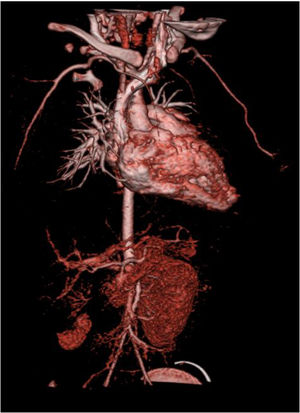

A chest X-ray revealed cardiomegaly with no pulmonary congestion. An electrocardiogram showed sinus rhythm, normal QRS axis, no pathological Q waves and inverted T wave in LI, LII and LIII. An echocardiography found dilatation of the left chambers with global left ventricular dysfunction, left ventricular ejection fraction (LVEF) 36%, left ventricular systolic function (LVSF) 17% and moderate mitral insufficiency, with coronary arteries of apparently normal origin (Figure 1).

For the next six months, BP remained stable with no need to initiate new drugs, and echocardiographic progress was favorable, with gradual improvement of left ventricular function. At 10 months of age, the patient underwent right nephrectomy without complications. Since then, gradual weaning from the drugs was possible. At 11 months of age, recovery of ventricular function was confirmed (LVEF 64%, LVSF 34%); the patient continued to have a very slightly dilated left ventricle (Figure 4).